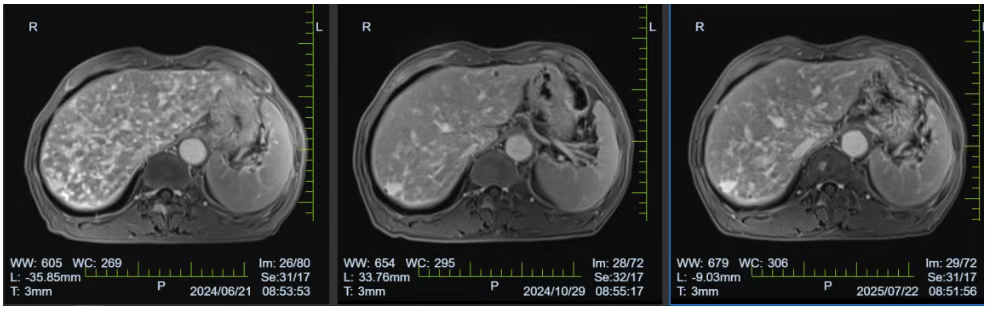

6 周期化疗后,患者全身转移病灶明显缩小,剧烈疼痛基本消失;

*肝脏增强MRI检查,提示病灶明显退缩

后续 11 周期维持治疗期间,病情持续稳定,肿瘤标志物显著下降,且未出现严重不良反应。如今,曾经被剧痛折磨得精神萎靡的李老先生,已实现疼痛消失、生活完全自理的高质量 “带瘤长期生存”。